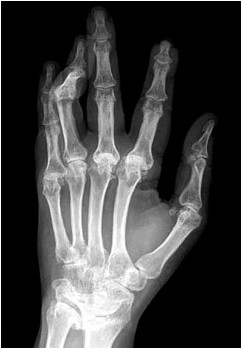

Paciente de 63 anos é avaliada com a radiografia mostrada a seguir:

Considerando a doença que cursa com a alteração mais relevante detectada no exame de imagem, constitui uma manifestação clinicamente evidente que, mais frequentemente, é encontrada nessa patologia a